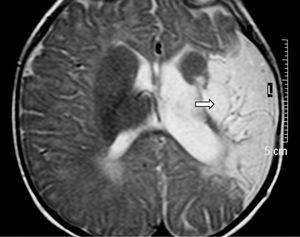

Se realizaron EEG y ecografía cerebral a las 24 h de vida que fueron normales. Ante la persistencia de la hipotonía, se realizó al quinto día de vida RM cerebral que mostró hallazgos compatibles con una lesión isquémica en el territorio arterial de la cerebral media bilateral, asociado a hemorragias subcorticales en dicho territorio, así como a nivel de sustancia blanca periauricular izquierda (fig. 3).

Figura 3.T1 coronal. Zona de infarto en fase hemorrágica en sustancia blanca paraventricular izquierda dependiente del territorio de la ACM izquierda. Áreas hemorrágicas corticosubcorticales del mismo hemisferio.